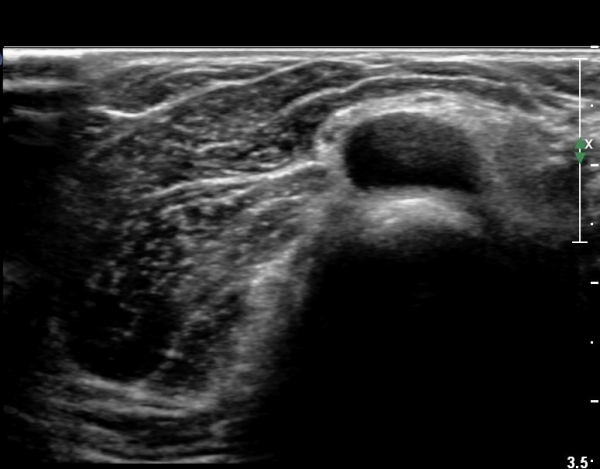

ŽÃÊÀÚ¸¦¸»´ÜÀ¸·Î  À̵¿ÇÏ´Ï ¿ä°ñ¸ñ ºÎÀ§¿¡¼­ Ä¿´Ù¶õ ³¶Á¾ÀÌ Èİñ°£ ½Å°æÀ» ¾Ð¹ÚÇÏ´Â °ÍÀÌ

°üÂûµÈ´Ù(»çÁø 4, 5)